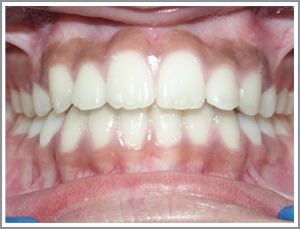

Case 1

Before

After

ABC a 16 year old girl had a deep bite and upper teeth which were inclined backwards and irregular

( Angles Class 1 malocclusion )

Problem list : unsightly teeth and damage to the gums due to the deep bite.

Treatment plan : Non extraction - She was treated without removal of teeth by pushing the teeth out slightly (proclining ).

Treatment time : 12 months